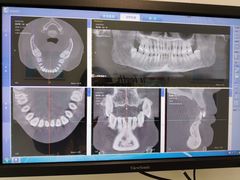

• Dr.Z dental仁康种植矫正中心

• -Dr.Z dental仁康种植矫正中心